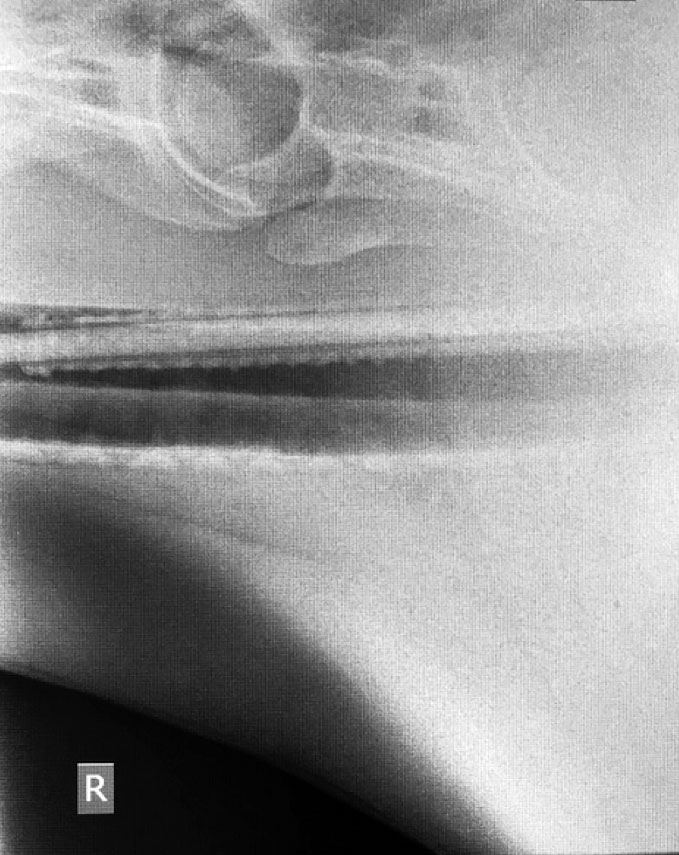

2019 They Ate What?! X-ray Contest winnersThey Ate This: Check out the winner, runners-up, and honorable mentions September 30, 2019 < Previous Entry Next Entry > Pages: 1 2 3 4 5 6 7 8 9 10 11 12 13 14